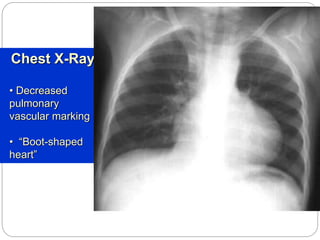

Chest X-Ray

• Decreased

pulmonary

vascular marking

• “Boot-shaped

heart”

 xray: boot shaped heart d/t RVH